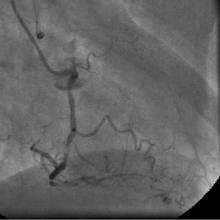

Angiography

1) RCA: Discrete severe mid stenosis (Figure 1)